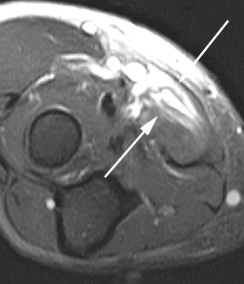

(Справа) На сагиттальной МРТ PDBИ определяется частичный отрыв сухожилия трехглавой мышцы с небольшим оторвавшимся костным отломком МРТ может быть информативна при оценке степени повреждения трехглавой мышцы. (Слева) На сагиттальной КТ с реформатированием можно видеть раздробление локтевого отростка после падения на локтевой сустав. Перелом открывается на суставную поверхность в нескольких местах.

3. МРТ при переломе локтевого отростка:

• Линия перелома лучше видна на сагиттальной и фронтальной Т1ВИ и Т2ВИ FS

• Стрессовое повреждение может определяться только по отеку костного мозга без линии перелома

• На МРТ можно не заметить небольшие переломы кончика

о МРТ для оценки целостности трехглавой мышцы

о МРТ: сагиттальная и осевая Т2ВИ для оценки перелома и целостности трехглавой мышцы